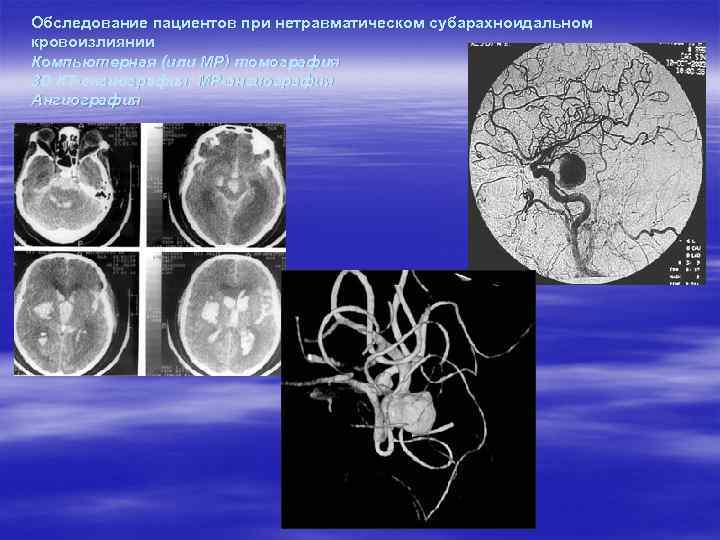

Обследование пациентов при нетравматическом субарахноидальном кровоизлиянии Компьютерная (или МР) томография 3 D КТ-ангиография, МР-ангиография Ангиография